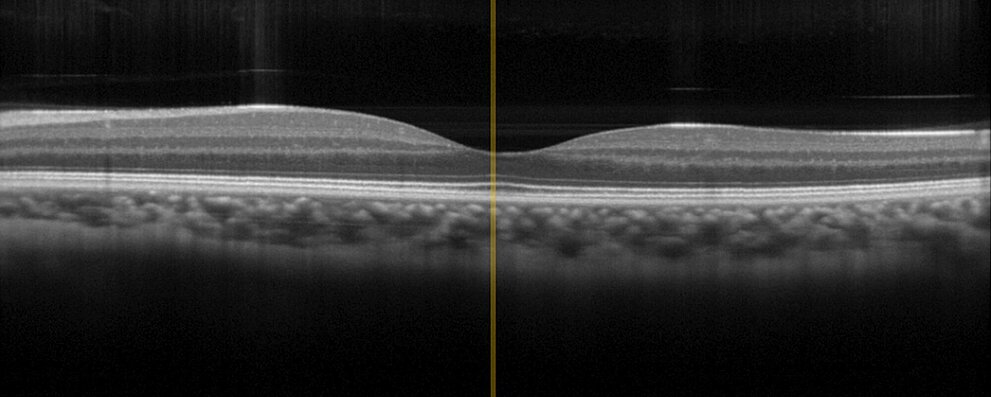

光学相干断层扫描(OCT)

借助光学相干断层扫描(OCT)技术,医生可以无创检查皮下层并创建皮肤结构的三维图像。这需要精密调整光学元件。